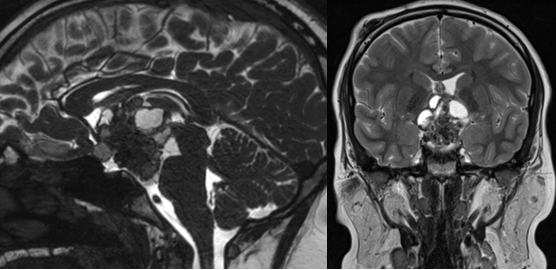

一位14岁患儿因视力模糊和剧烈头痛就诊,检查发现一个位于视交叉后方、伴有钙化的颅咽管瘤。主刀医生Rutka教授首先为患儿进行了脑室-腹腔分流术,缓解脑积水;随后通过内镜经鼻入路完成肿瘤全切。术后患儿视力显著改善,开始接受激素替代治疗,至今未见复发。

术前